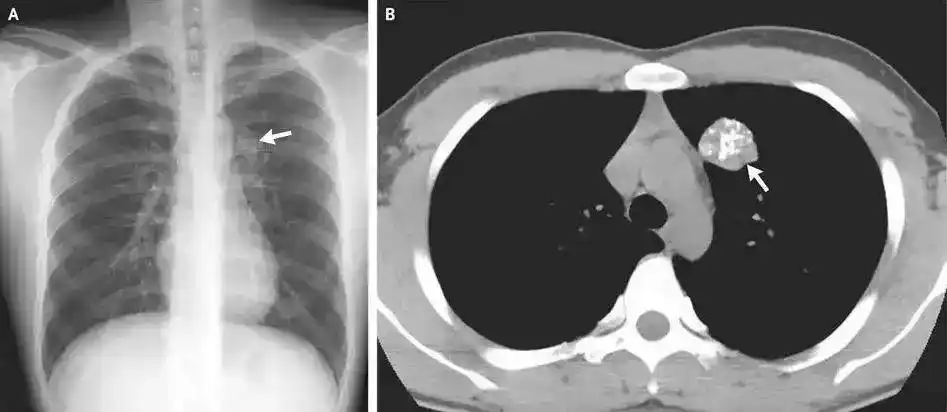

事实上,在X线片、CT、钼靶、超声报告中,常常会出现“钙化”“钙化灶”的字样。

人体绝大部分组织和器官内都可能出现钙化,比如头颅的脑膜、基底节区,胸部的肺、肋软骨、胸骨剑突,腹部的肝脏、肾脏,以及甲状腺、乳腺和前列腺等腺体,还有遍布身体的大多数动脉和静脉血管。钙化存在的广泛性也使得它成为体检和平时检查中影像学报告上的“常客”。

航空总医院影像科副主任申太忠介绍:“钙化不是疾病,而是一种体征。”钙化是否影响健康要根据其出现的部位、影像学特点、患者临床表现来确定。

疾病:某些慢性疾病可能诱发钙化,比如糖尿病长期未得到有效控制,会导致高血糖和代谢紊乱,并影响肾脏对钙的排泄和代谢,引起钙化。疾病的修复和愈合也可能导致钙化,比如结核性肺炎病变区域的组织,就可能在炎症后的修复过程中形成钙化。